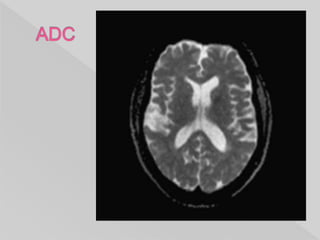

 representing the actual diffusion values of

the tissue without T2 effects.

 much more useful, and objective measures

of diffusion values can be obtain.

 grayscale inverted DWI images.

 They are relatively low resolution images

with the following appearances:

 grey matter: intermediate signal intensity

(grey)

 white matter: slightly hyperintense compared

to grey matter

 CSF: high signal (white)

 fat: little signal due to paucity of water

 other soft tissues: intermediate signal

intensity (grey)

 Acute pathology (ischemic stroke, cellular

tumor, pus) : decreased signal denoting

restricted diffusion.

Low ADC values is seen

involving the right-sided basal

ganglia and cortex of the MCA

and ACA territories of the right

cerebral hemisphere.